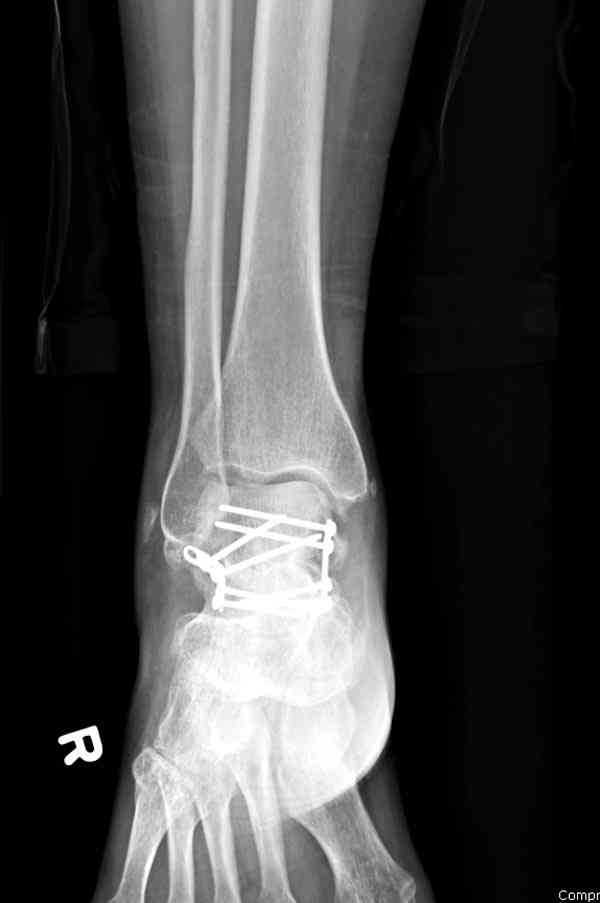

Решили не связываться с остеосинтезом, а сделать сразу берцово-пяточный блок. Снимки в приложении.

По завершении удлинения, наверно, заштифтуем.

Комментарии/критика приветствуются.